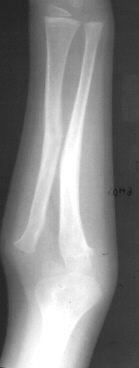

This is a 4 + 6mos old male who sustained a fall onto an outstretched left arm in December 1994 resulting in a Monteggia Type lV fracture. It was treated with closed reduction and casting. Subsequently, he went on to a malunion with a persistent dislocation of the radial head. He presented to A.I. duPont Institute10 months post injury for further evaluation and treatment.

XRAY FINDINGS:

The most important view is a true lateral of the elbow. The lesion may be missed on the AP view. In the lateral view, a line drawn through the center of the radial neck and head should extend through the capitelum. This is true whether the elbow is flexed or extended.